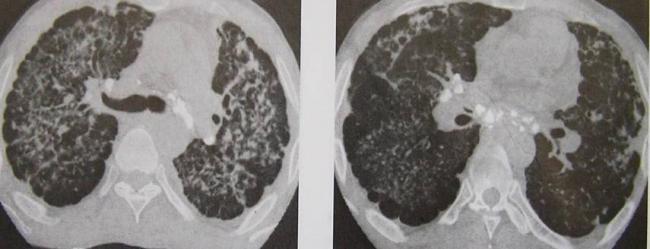

Очаговые изменения

Очаговые изменения в лёгких могут быть разного размера. Очаги мелкого диаметра 1-10 мм выявляются при различных диффузных патологиях лёгочной ткани. Очаги с высокой плотностью и довольно чётки краями в основном наблюдаются в интерстиции лёгкого. Различные очаги низкой плотности, напоминающие матовое стекло, с нечёткими контурами возникают при патологических изменениях в респираторных отделах дыхательных органов.

Нужно учитывать, что плотность и размер очагов имеет слабое диагностическое значение. Для постановки диагноза более важным может быть распределение патологических процессов в лёгочной ткани:

- Перилимфатический очаг – часто наблюдается в бронхах, сосудах, в междольковых перегородках и листках плевры. В таком случае видны неровные контуры анатомических структур, при этом перегородочки и стенки бронхов несколько утолщены, как и стенки сосудов. Подобные патологические изменения часто встречаются при туберкулёзе, силикозе, саркоидозе и карциноматозе. При этих патологиях очаги небольшие и не превышают 2-5 мм. Состоят такие очаги из гранулем или метастатических узелочков, они наблюдаются вдоль лимфатических узелков в ткани лёгких и плевре.

- Полиморфный очаг. Такие очаговые образования в ткани лёгких возникают при туберкулёзе. В этом случае КТ позволяет увидеть участки разной плотности и размеров. В некоторых случаях такая картина наблюдается при онкологических патологиях.

- Центрилобулярные очаги. Наблюдаются в артериях и бронхах или в непосредственной близости от них. Они могут быть довольно плотными, хорошо очерченными и однородными. Изменения лёгочной ткани такого типа наблюдаются при пневмониях, эндобронхиальном туберкулёзе и разных видах бронхита, преимущественно бактериального происхождения. Есть и другой тип центрилобулярных очагов, в этом случае лёгочная ткань имеет мелкие уплотнения и похожа на матовое стекло.

- Периваскулярные очаги – это патологические образования, которые находятся в непосредственной близости от кровеносных сосудов. Такое состояние наблюдается при онкологических патологиях и туберкулёзе. Очаги могут быть как единичные, так и множественные.

- Хаотично расположенные очаги. Такие образования характерны для патологических гематогенных процессов. Это может быть гематогенная инфекция, туберкулёз или метастазы гематогенного типа. Большие множественные очаги, размером около 10 мм, частенько наблюдаются при септических эмболиях, гранулематозе, грибковых инфекциях и метастазах. Все эти заболевания имеют некоторые отличия, по которым их можно дифференцировать.

- Субплевральные очаги – это патологически изменённые участки, расположенные под плеврой. Наблюдение таких участков на снимке всегда говорит о развитии туберкулёза или онкологических заболеваний.

- Плевральные очаги. Такие патологические образования расположены на плевре. Наблюдаются при воспалительных и инфекционных патологиях нижних дыхательных органов.

- Апикальный очаг представляет собой чрезмерное разрастание фиброзной ткани, которая со временем замещает здоровые клеточки.

- Лимфогенный карциноматоз. Это понятие включает два типа патологических изменений в лёгких. С правой стороны наблюдается альвеолярная инфильтрация, с видимыми просветами бронхов. С левой стороны плотность лёгочной ткани несколько повышена. В зоне уплотнения наблюдаются стенки бронхов и сосудиков.

При очаговых заболеваниях участки патологически изменённой ткани могут быть разными по размерам. Они могут быть мелкими, размером не более 2 мм, средними – диаметром до 5 мм и крупными, размер последних превышает 10 мм.

Патологические очаги бывают плотными, средней плотности, а также рыхлыми. Если в лёгких наблюдаются единичные уплотнения, то это может быть как возрастным изменением, которое не представляет опасности для человека, так и опасным заболеванием. Если наблюдаются множественные очаги, то здесь речь идёт о воспалении лёгких, туберкулёзе или редких формах онкологических заболеваний.